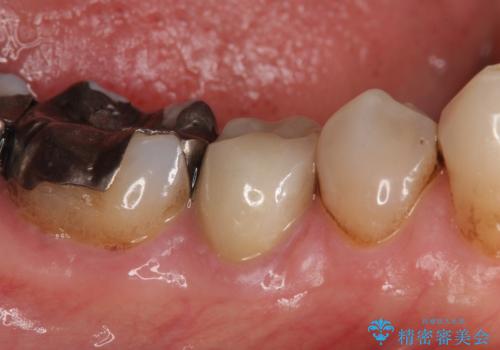

- 右下の歯でものを咬むと違和感があるので診て欲しいといらっしゃった方の症例です。

右下5番目の歯に根尖病変を認めたため、再根管治療を行い、オールセラミッククラウンによる補綴を行いました。

今回用いたオールセラミッククラウンは、ジルコニアフレームという白い素材の上にセラミックを盛っているため審美性が非常に高いのが特徴です。

またジルコニアは人工ダイヤモンドの材料にも使われているほど高い強度を持っており、そのためオールセラミッククラウンは審美性だけでなく、奥歯やブリッジの補綴も可能とするクラウンです。